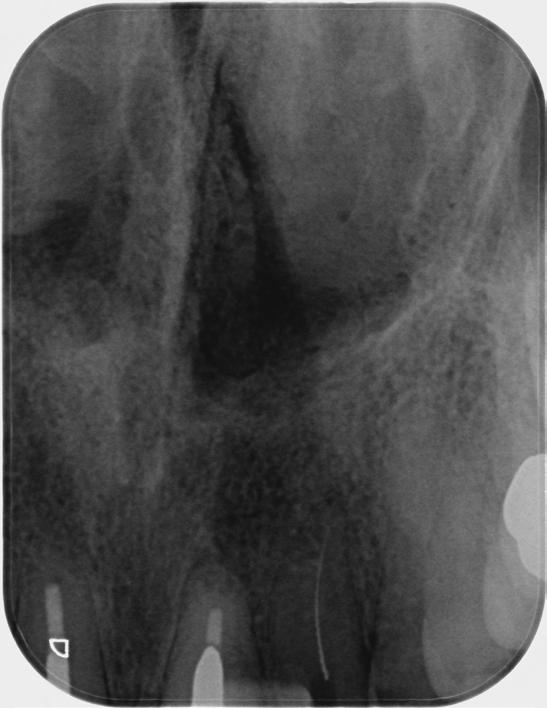

Based on the clinical and radiographic findings, tooth 22 was diagnosed as necrotic with a possibly infected root canal system (RCS), pulp canal calcification and primary acute apical periodontitis due to decay, cracks and restoration breaking down. An endodontic investigation procedure was planned to determine whether the 22 was suitable for further restoration. While the treatment was supposed to be straightforward initially, it progressed to become very complex surprisingly. This was due to separation of a size-10 H-file in the root canal of tooth 22.

The instrument separation was first noticed after taking the initial radiograph to establish the working length. It probably happened due to the patient biting inadvertently on the file during x-ray exposure. As our patient was a bruxer, his bite forced the file deeper in the

severely calcified root canal. The file was now firmly stuck inside the root canal. Despite trying to gently retrieve the file, it broke at junction of the cutting surface to the shank. Bypassing and/or retrieval procedures were planned and performed by using hand files, rotary files and Satelec ultrasonic tips in three different sessions, each one almost three hours long. Rotary files were used mainly as adjunctive instruments.

Taking advantage of rotary files made of a heat-treated alloy with minimal cutting efficiency, designed in a way to scrape rather than cut the dentin, enabled me to safely enlarge the space made by the hand files. This technique also participated in less frequency and chance of breaking more files next to the broken file.

Finally, the broken file segment was removed with braiding barbed broaches around the file. Notably, the patient patiently cooperated all throughout the treatment.

I had a thorough discussion with the patient about the reasons why this incident happened. Even though I could have simply pointed out a severely calcified root canal or a heavy bite to be responsible for the incident, I concluded that the patient’s occlusion should have been assessed carefully during case assessment in order to set preventive measures, which in turn could have potentially saved the patient and I from all the consequences.

Take home message - ALWAYS check your patient’s occlusion during the first examination/ consultation session. It will save you a lot of money!

Fig.1 File got stuck (22/09/2023) Fig.2 File fractured (22/09/2023)

Fig.4 Cut the file deeper (22/09/2023)

Bypassed to WL (12/10/2023)

And even deeper (12/10/2023)

Fig.3 Made space coronally (22/09/2023)

Fig.6 Rotary files used (12/10/2023)

Fig.8 Finally retrieved the file (12/10/2023)